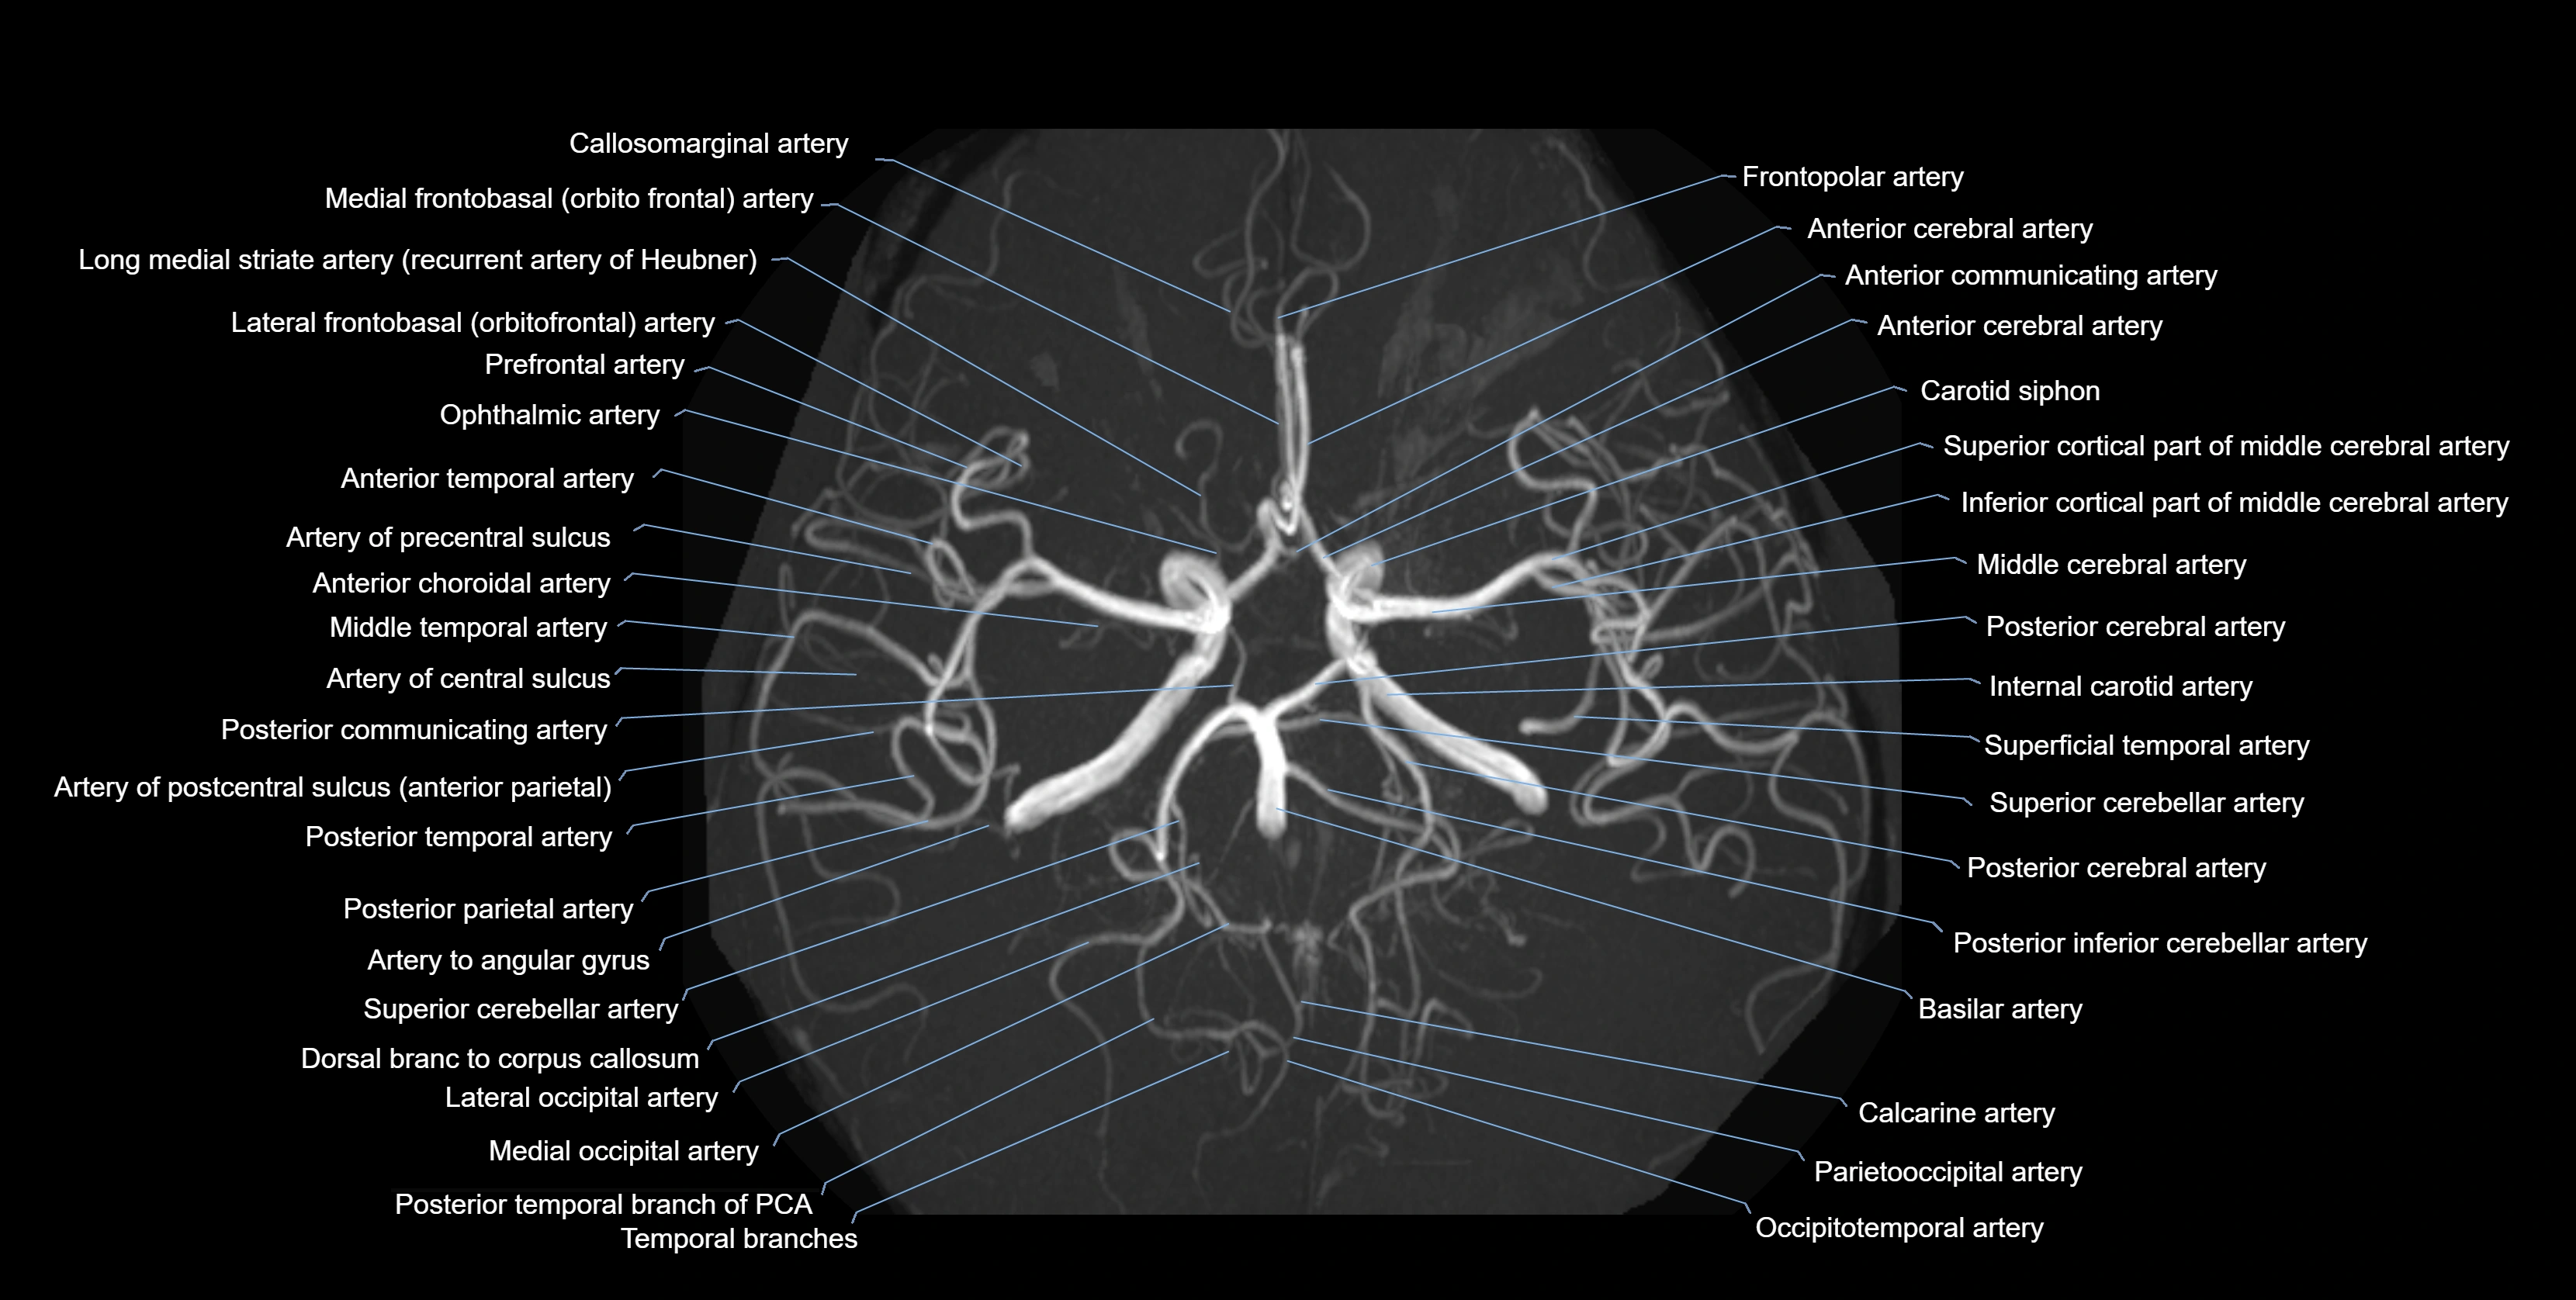

MRA (Magnetic Resonance Angiography):

• Flow-related enhancement makes the AChA appear as a bright, linear vascular signal against suppressed background

• High sensitivity for origin and proximal course; distal branches may be too small to resolve

• Detects stenosis, occlusion, aneurysm, AVM feeders

CTA (CT Angiography):

• Opacified with iodinated contrast, AChA appears as a bright high-attenuation vessel

• Visualized from ICA origin along optic tract toward choroid plexus

• 3D reconstructions depict its course and relation to adjacent arteries

• Gold standard for identifying aneurysms, occlusion, or vascular anomalies